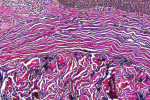

The histologic evaluation showed collagen that aligned horizontally, in a mostly parallel nature, to the superficial epithelium in both the ungrafted (Figure 10 and Figure 11) and grafted (Figure 12 through Figure 15) biopsy sites. In the grafted specimens, a clear demarcation at the interface of the native tissue and the implanted tissue was present. The implanted tissue, which was characterized by dense bands of disorganized collagen matrix, appeared well incorporated and without inflammatory cells. The Verhoeff's stain demonstrated the presence of numerous darkly stained elastin fibers in the implanted tissue that were inconspicuous in the native tissue.

The H&E and Verhoeff's stains allowed the collagen architecture of the native tissue to be clearly distinguished from that of the implanted tissue. The superficial native tissue exhibited collagen fibers that aligned parallel to each other and the epithelium, whereas the implanted tissue exhibited collagen fibers that appeared disordered. The implanted tissue, however, was markedly thicker than the overlying native tissue. Verhoeff's stain, which stains elastin fibers, has been used to identify implanted ADMs in grafted GRD sites.1,4,15 In this case, the abundant darkly stained elastin fibers in the grafted specimen indicate that the hydrated ADM was incorporated and not absorbed or exfoliated. The absence of observable inflammatory cells indicated that the implanted hydrated ADM was immunologically inert.